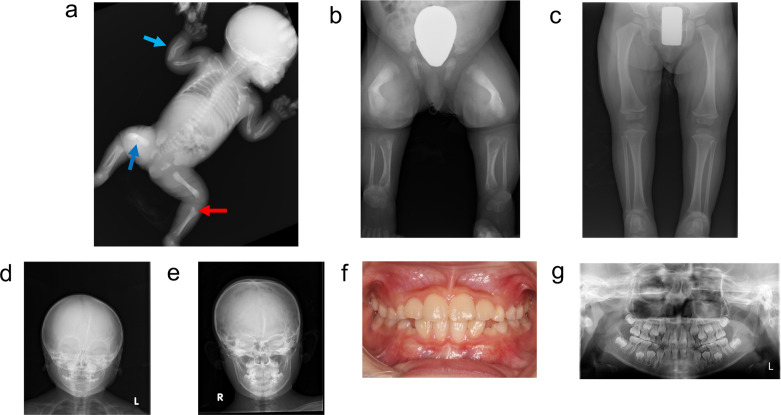

低磷酸症(HPP)是一种遗传性疾病,其特征是由组织非特异性碱性磷酸酶(TNSALP)活性降低引起的骨矿化受损。具体来说,HPP是由编码TNSALP的ALPL基因的功能丧失变体引起的。尽管基因型-表型相关性已被描述,但表型差异已被报道在具有相同变异的患者中,甚至在家庭内。先证者,一名女孩,被怀疑在子宫内有长骨骨折,暗示成骨不完全。出生后未见呼吸障碍;但患者血清碱性磷酸酶水平较低。此外,患者的围产期表现与围产期良性HPP一致,尽管随后骨骼症状恶化。患者的兄弟最初因乳牙过早脱落而怀疑患有牙髓- hpp,后来出现压缩性骨折和骨外症状。两例患者均有相同的ALPL变异,c. 572A>G(;)1559del, p. Glu191Gly(;)Leu520ArgfsTer86;然而,他们的病情严重程度有所不同。同一家族中具有相同基因型的HPP患者可能具有不同的HPP严重程度。在本病例报告中,两名患者均接受了酶替代治疗(ERT),改善了临床症状。因此,对于围产期良性HPP,如果骨骼症状加重,应考虑ERT。此外,应密切监测牙髓- hpp,如果出现骨和骨外症状,应考虑ERT。

Hypophosphatasia (HPP) is a hereditary disorder characterized by impaired bone mineralization caused by decreased tissue-nonspecific alkaline phosphatase (TNSALP) activity. Specifically, HPP is caused by a loss-of-function variant in the ALPL gene encoding TNSALP. Although genotype-phenotype correlations have been described, phenotypic differences have been reported in patients with the same variants, even within families. The proband, a girl, was suspected to have in utero fractures of the long bones, suggestive of osteogenesis imperfecta. No respiratory impairment was observed after birth; however, the patient's serum alkaline phosphatase level was low. In addition, the patient's perinatal findings were consistent with those of perinatal benign HPP, although the bone symptoms subsequently worsened. The patient's brother, initially suspected to have odonto-HPP due to the premature loss of primary teeth, later developed compression fractures and extraosseous symptoms. Both patients had the same ALPL variants, c. 572A>G(;)1559del, p. Glu191Gly(;)Leu520ArgfsTer86; however, the severity of their conditions differed. Patients with HPP with identical genotypes in the same family may have varying severity levels of HPP. In this case report, both patients received enzyme replacement therapy (ERT), which improved the clinical symptoms. Therefore, for perinatal benign HPP, ERT should be considered if bone symptoms worsen. In addition, odonto-HPP should be closely monitored, and ERT should be considered if bone and extraosseous symptoms arise.